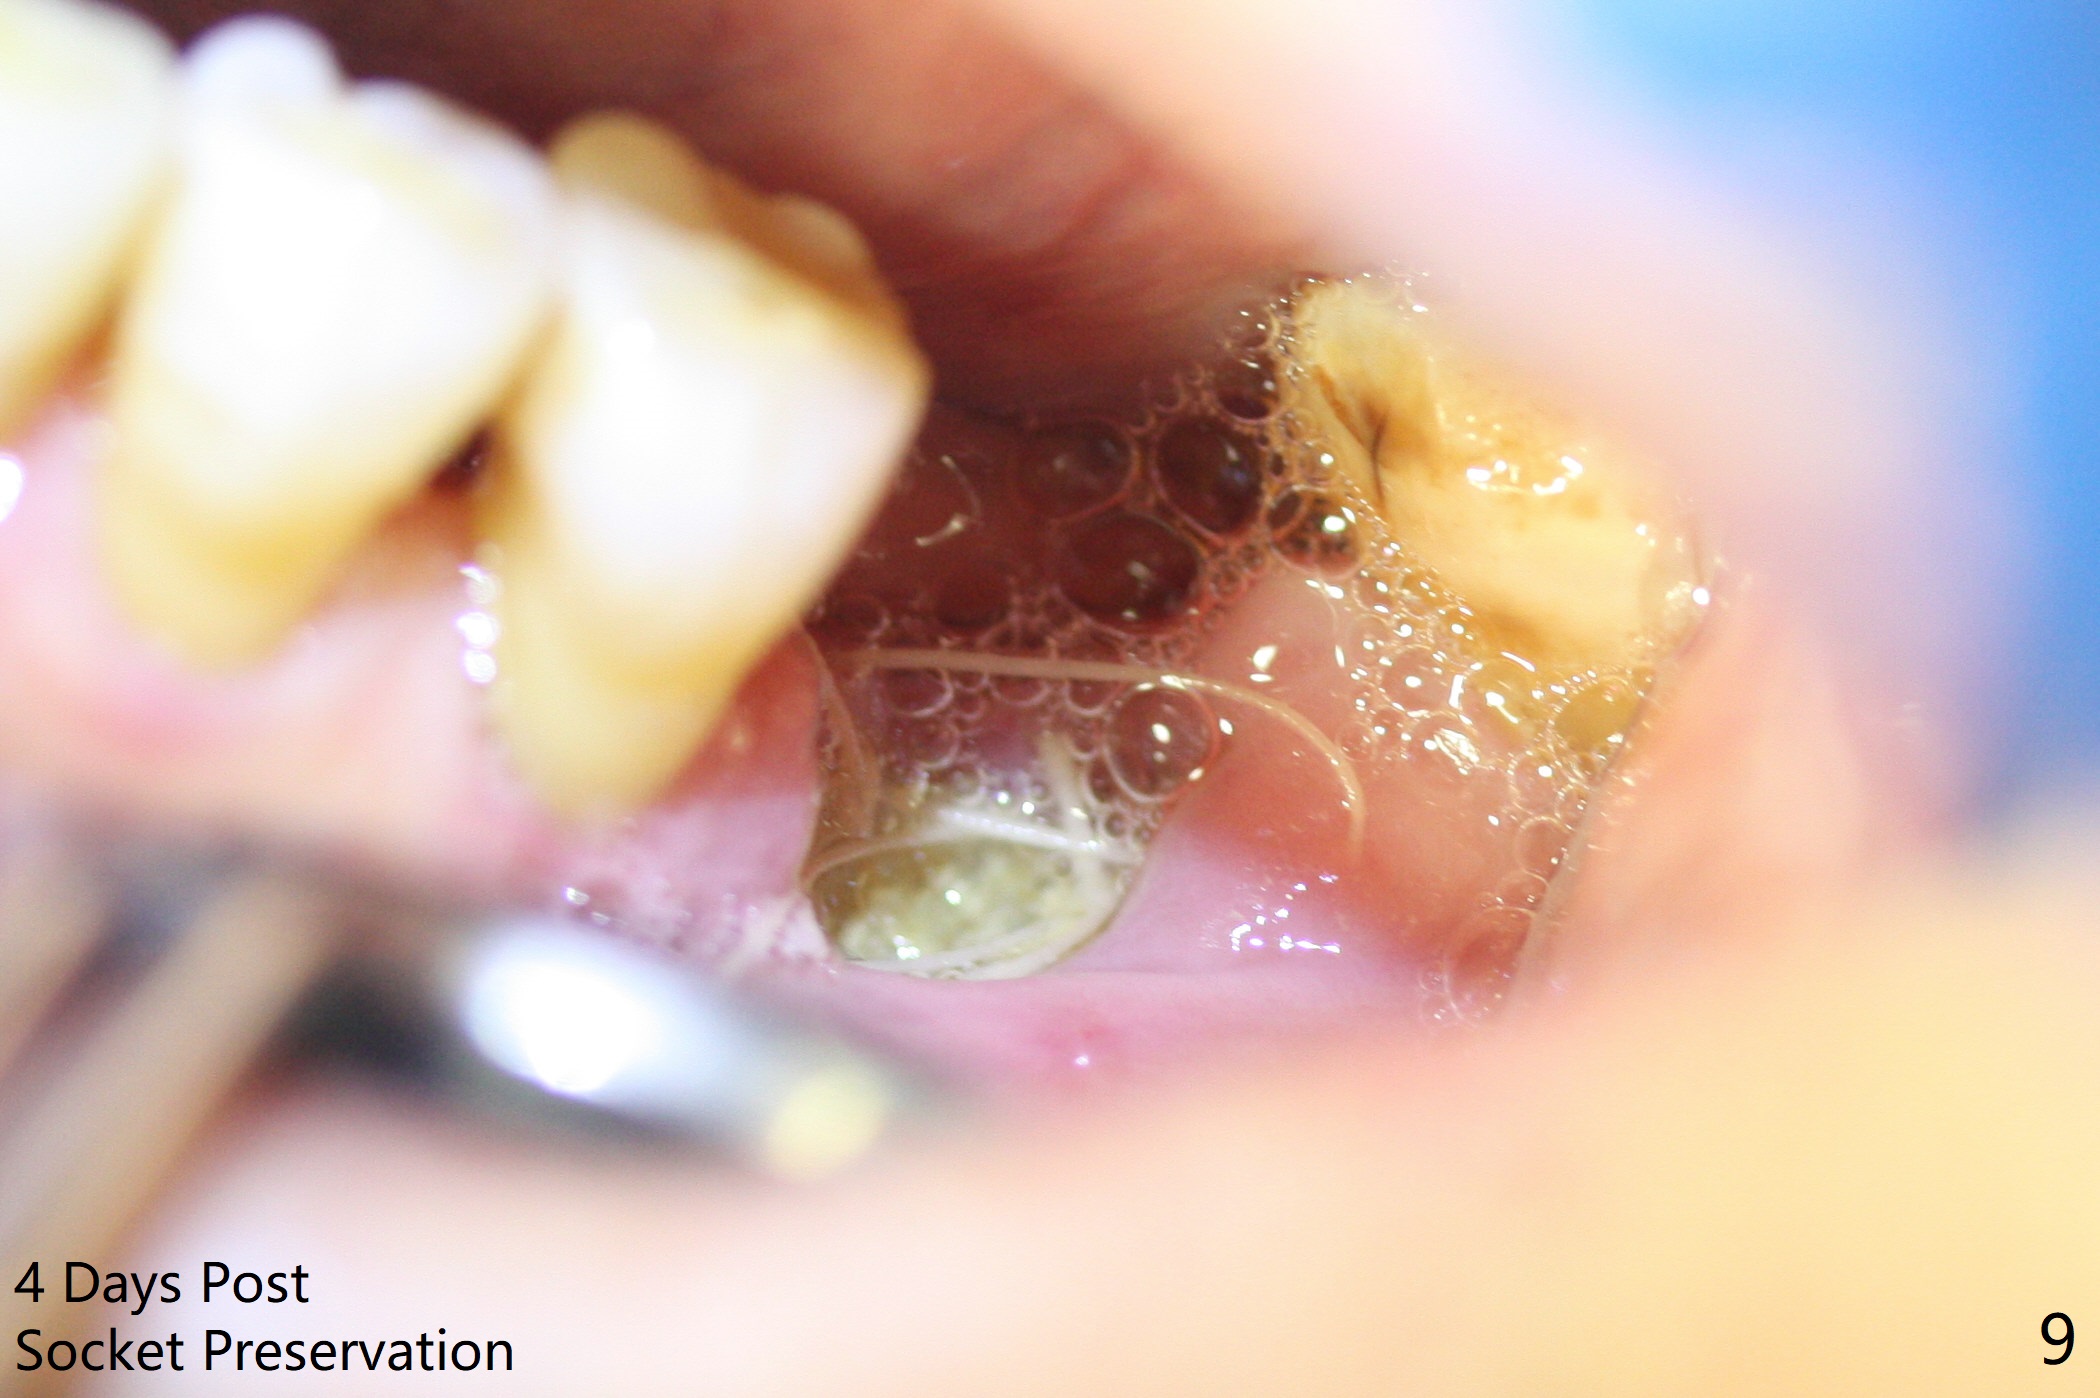

A 63-year-old man is a diabetic with history of good control. He masticates unilaterally with missing teeth #2,3 and 24 (Fig.1 (taken 5 years ago)). The latter has been restored with an implant. Last February the mesial root of the tooth #19 was found to have vertical fracture with bone loss until the base of the septum (Fig.2). The bone available for implantation is ~7-8 mm after root fracture (Fig.3,4). The initial osteotomy depth will be 7 mm (IS kit), followed by the calibrated parallel pin. The latter determines how many millimeters of an implant will be surrounded by the graft bone (Fig.4,5 (green: implant length; pink: cuff; blue: abutment length)). Since the buccal defect is severe with mesial root split (Fig.7 *), draw blood for PRF (2 large tubes). To save the remaining septum, place 2 of 1-piece implants on the either side of the septum (compare Fig.6,8). Take photos to compare buccal vs. lingual gingival recession. Tell the patient that the tooth #20 may be nonsalvageable. Since insurance preauthorization does not get approval for several times, the tooth #19 is extracted with socket preservation and periodontal dressing. The latter dislodges in 1 day. When the patient returns for follow up 4 days postop, the socket is exposed (Fig.9). An immediate implant should have been placed to keep the graft in place. PRF also helps. In fact preauthorization letter arrived 1 day earlier. It appears that guided surgery is indicated for limited bone height. The bone graft appears to gain ~ 5 mm bone in 4 months (Fig.10), which allows to place a 5x8.5 mm implant (Fig.11).